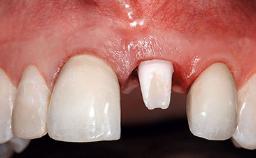

Replacement of an Upper Right Central Incisor with a Root Fracture, Early Placement of an RC Bone Level Implant, Variobase Abutment

Prosthesis Type | FDP |

Provisional Implant-Supported Prosthesis | Prosthodontic margin > 3 mm apical to mucosal margin Prosthodontic margin > 3 mm apical to mucosal margin |